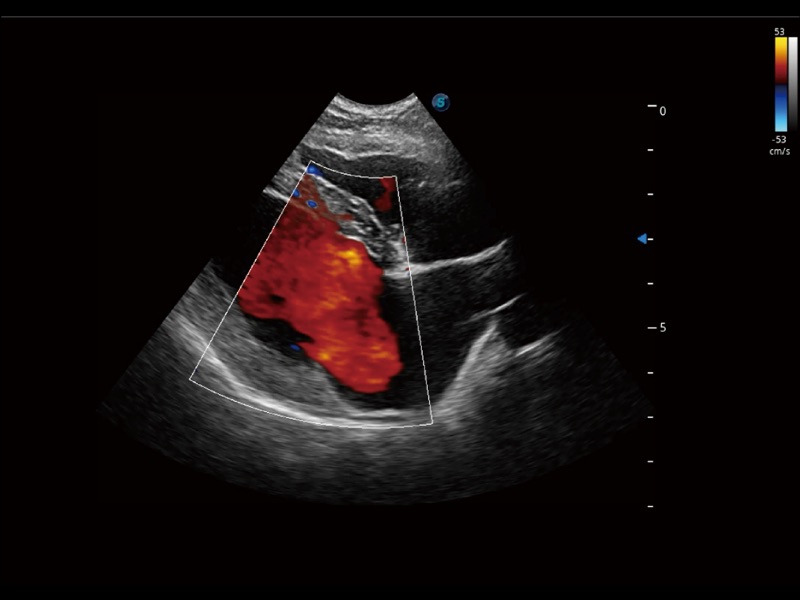

能够基于左心室壁追踪和辛普森法,自动计算射血分数,支持多个可移动点描迹,与手动测量相比,极大节省了动物医生的时间和精力。

通过360度任意调节3条M型取样线,在同一心动周期上观察心脏不同位置的运动曲线,得到准确的心功能测量数据,有效评估心肌运动及左心室功能。

实时用颜色表示心肌组织运动,观察和定量组织的运动情况,对快速检测与评估心肌的灌注和活性、电传导及心肌收缩和舒张功能等均能提供重要的诊断信息。